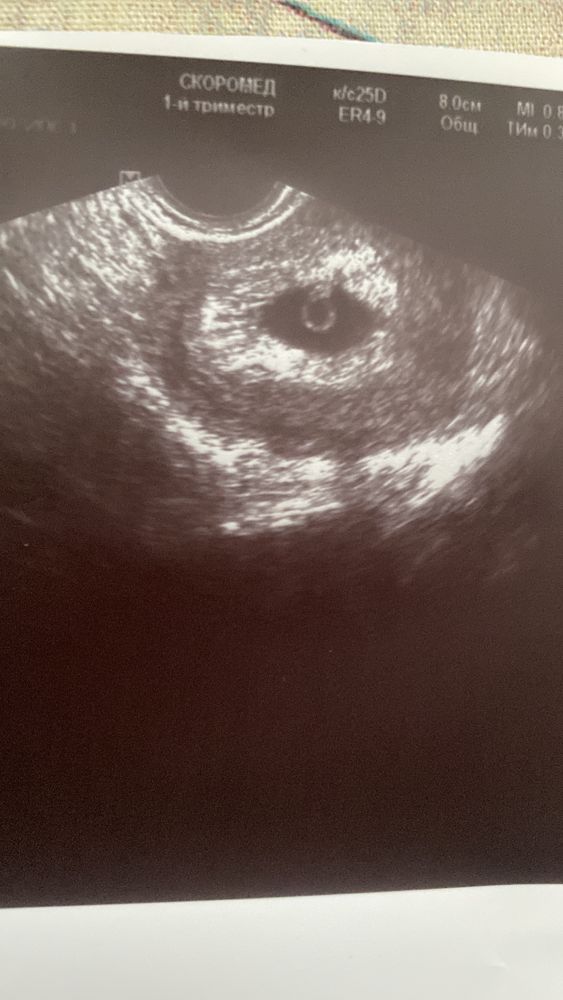

Узи на 32дпп ктр 3 мм

Ирина, жм 3,5, пя 18 мм

Пока рано переживать. Через 3-5 дней узи переделайте и смотрите, растет ли ктр. Сердцебиения при таком размере ктр еще не будет, так что на это не смотрите